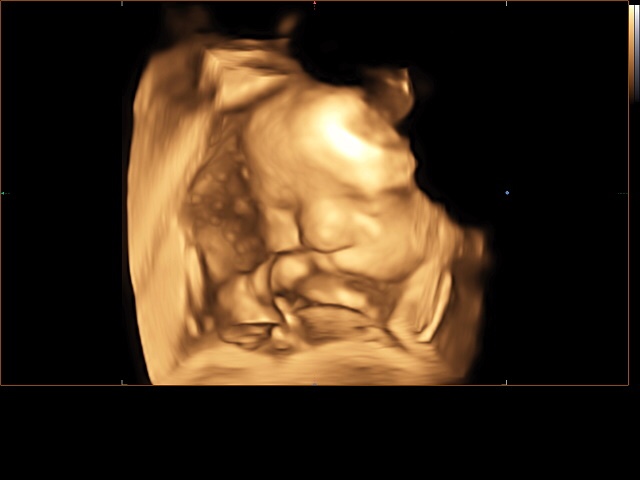

А вот и наш третий скрининг)))) все в норме! По весу 1800. Врач сказала хороший щекастый мальчик с большой морковкой 😂😂😂😂

Делали 4д с записью на диск видио и фото